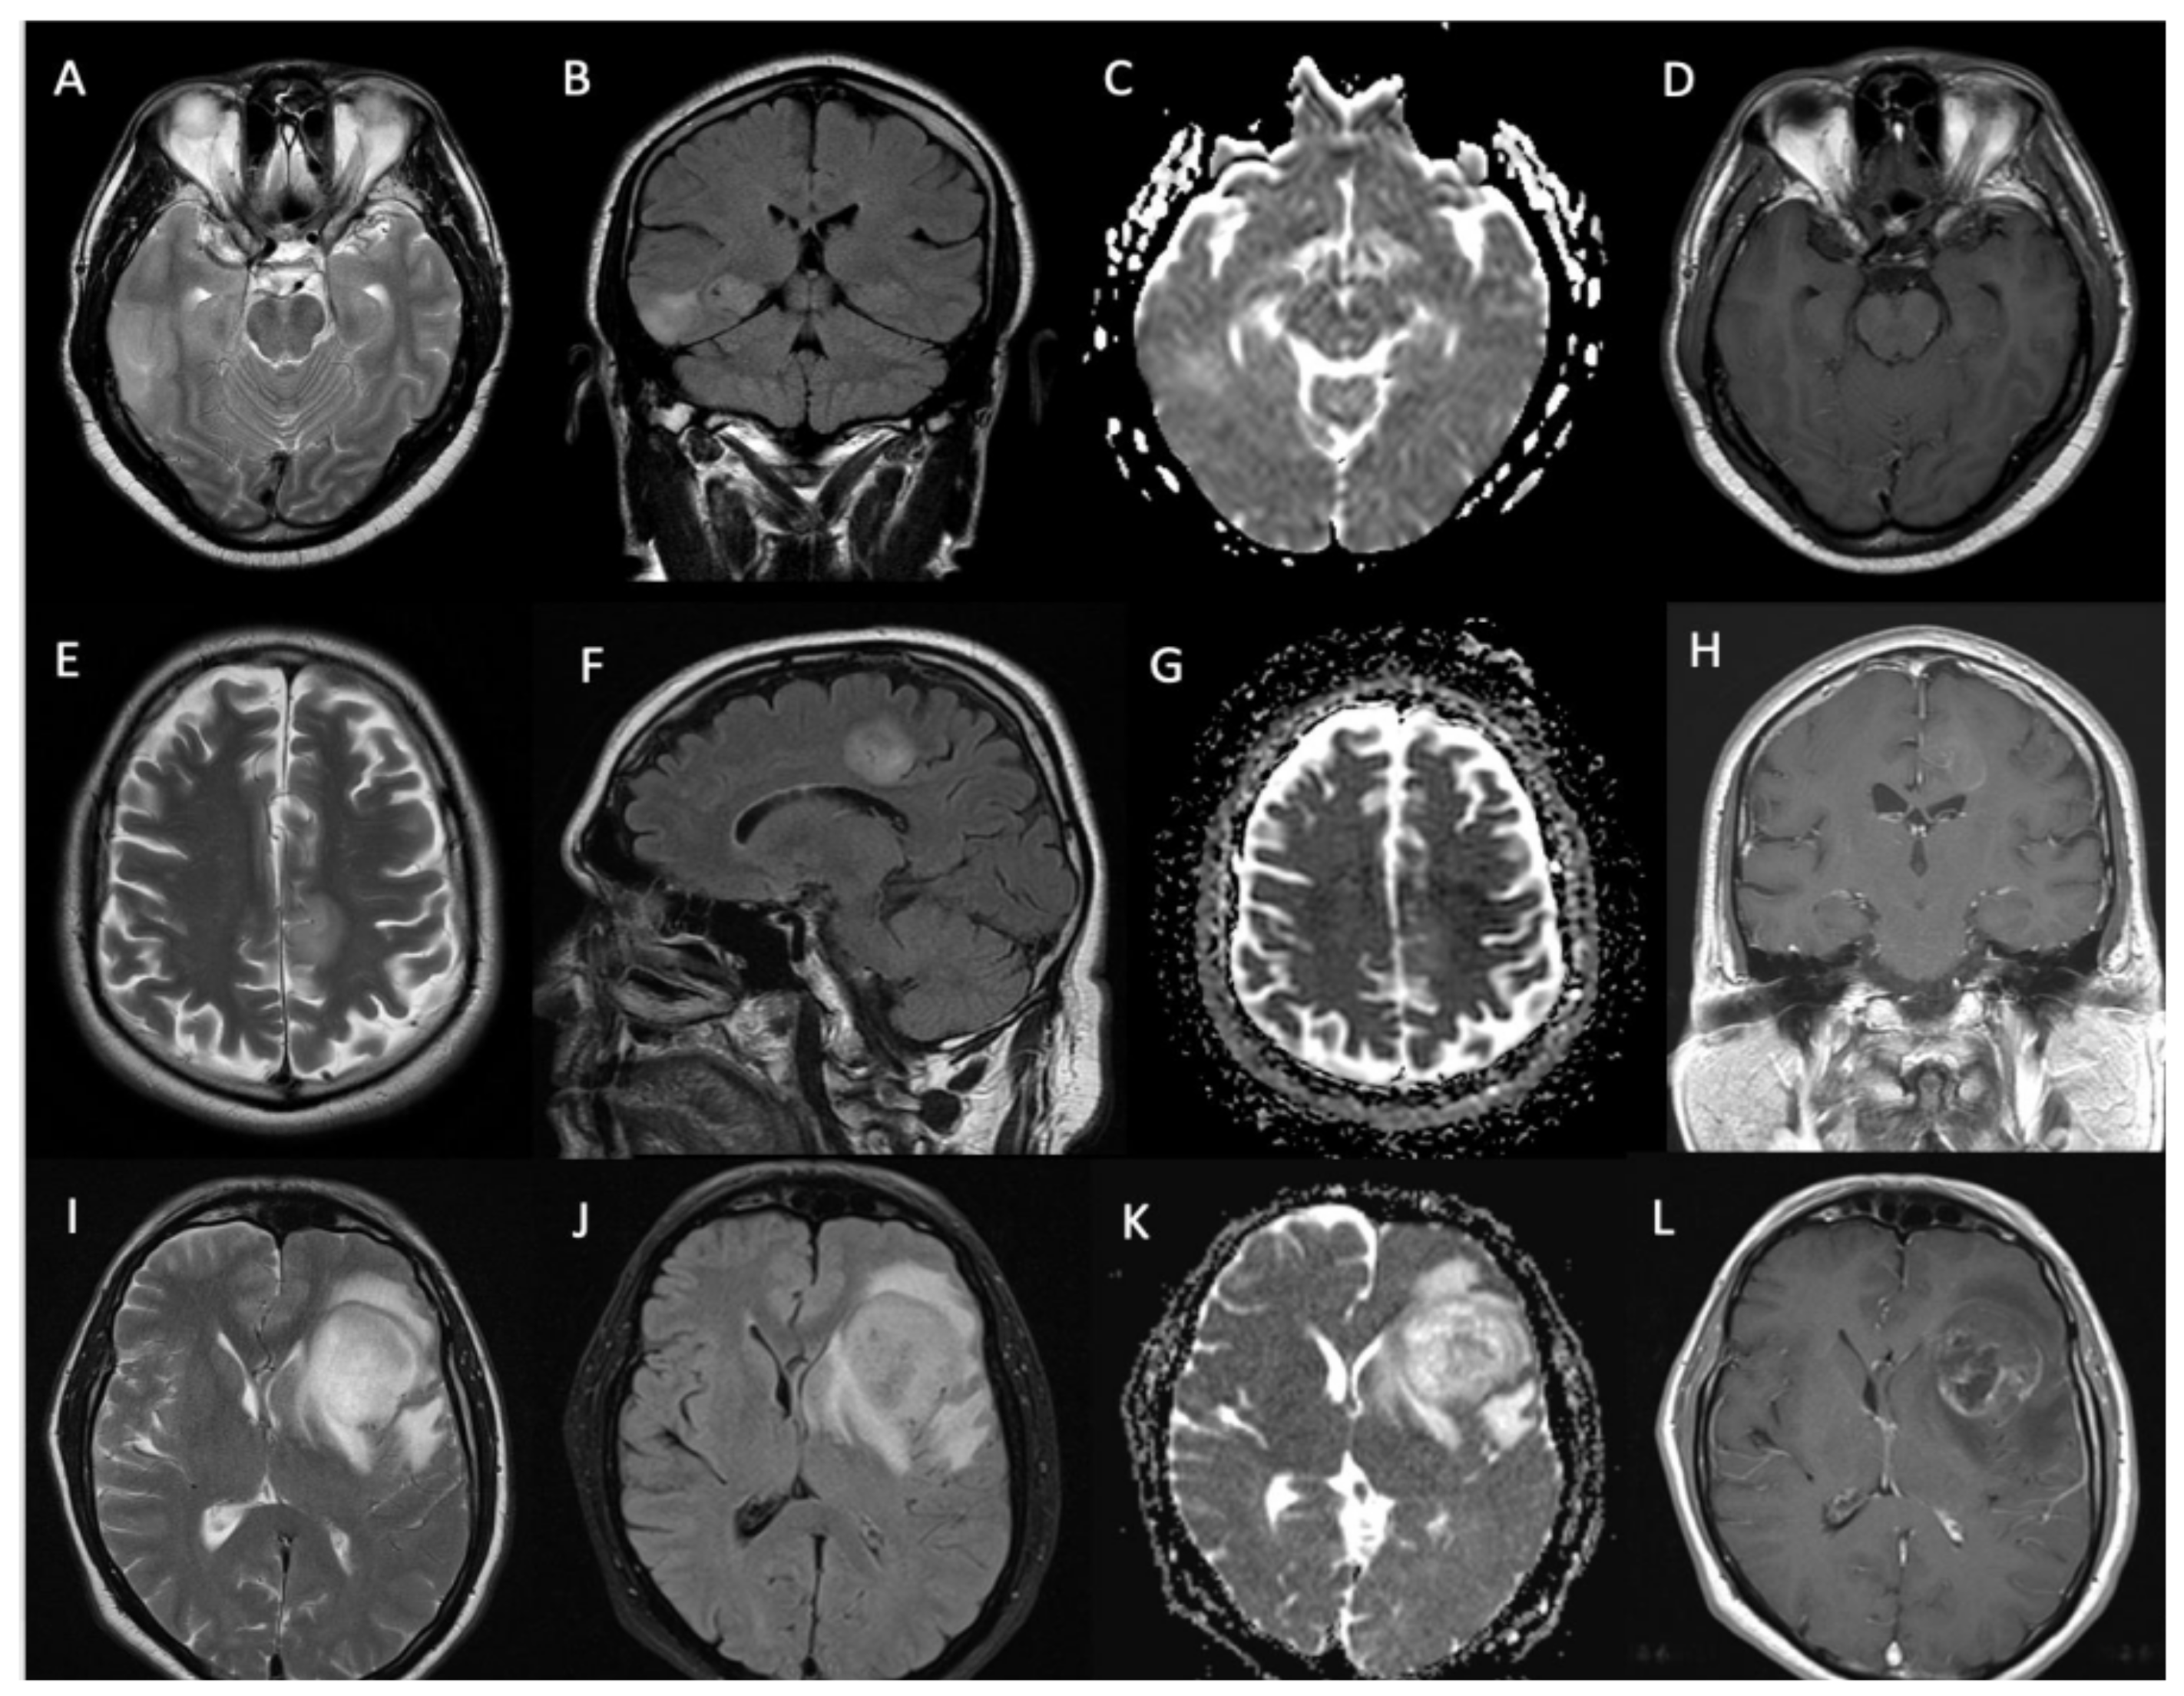

| Contrast enhancement | |

| Solid pattern | 18 (33%) |

| Rim enhancement | 17 (31%) |

| Non-enhancing | 19 (36%) |

| Contrast enhancement on diagnostic MRI (present vs. absent) | 15.2 (12.1 to 18.3) vs. 28.8 (21.3 to 36.2) months | p = 0.003 |

| Pattern of gadolinium enhancement (solid/patchy versus rim-enhancing with central necrosis) | 15.9 (12.5 to 19.3) vs. 14 (11.7 to 16.2) months | p = 0.57 |